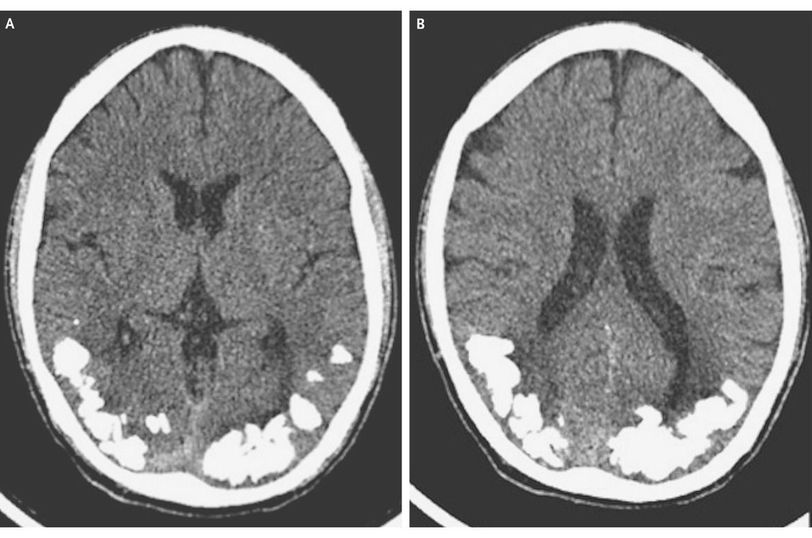

A 24-year-old man presented with a 10-year history of recurrent episodes of throbbing, occipital headache associated with complex visual symptoms, lasting from a few minutes to an hour. He had been treated for migraine, with little response. Routine blood tests revealed a mildly decreased folate level (2.2 ng per milliliter [5.0 nmol per liter]; reference range, 3.1 to 17.5 ng per milliliter [7.0 to 39.0 nmol per liter]), and a computed tomographic scan of the head revealed bilateral occipital calcification (Panels A and B). Laboratory testing revealed normal cerebrospinal fluid and elevated levels of serum IgA antitransglutaminase antibodies (45 U per milliliter; reference range, <10) and antiendomysial antibodies (titer, 1:40). He underwent endoscopy, and pathological evaluation of a jejunal-biopsy specimen revealed crypt hyperplasia, villous atrophy of the jejunal mucosa, and an increased number of intraepithelial lymphocytes. Treatment with a gluten-free diet, folic acid supplementation, and carbamazepine was initiated, and the patient's condition improved, with remission of all symptoms. The combination of celiac disease, epilepsy, and cerebral calcification is a rare condition known as the CEC syndrome. Folate malabsorption is a suggested mechanism, because cerebral calcification can be seen in other conditions related to folate deficiency, such as treatment with methotrexate, congenital folate malabsorption, and the Sturge–Weber syndrome.